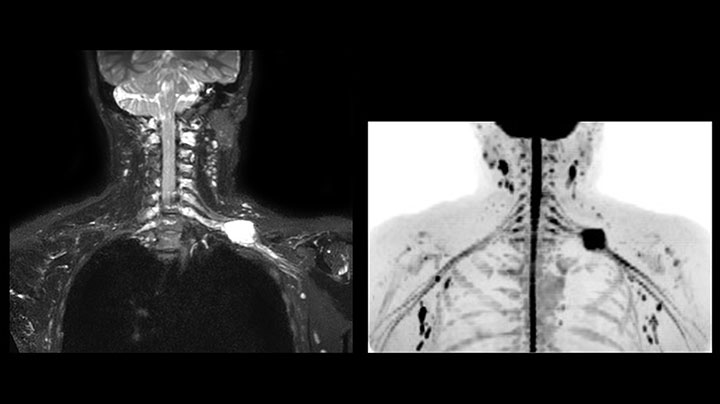

MR neurography of nerve sheath lesion

This patient is a 43-year-old female with a left supraclavicular nerve sheath tumor. The lesion is well visualized on the STIR VISTA images and on the MR neurography using DWIBS. The exam was performed on Prodiva 1.5T.

Whole body diffusion

MR neurography using DWIBS inverted, full MIP

Acq voxel size 1.2 x 1.3 x 2.4 mm, Recon voxel size 0.7 x 0.7 x 1.2 mm, dS SENSE factor 2, scan time 5:46 min.